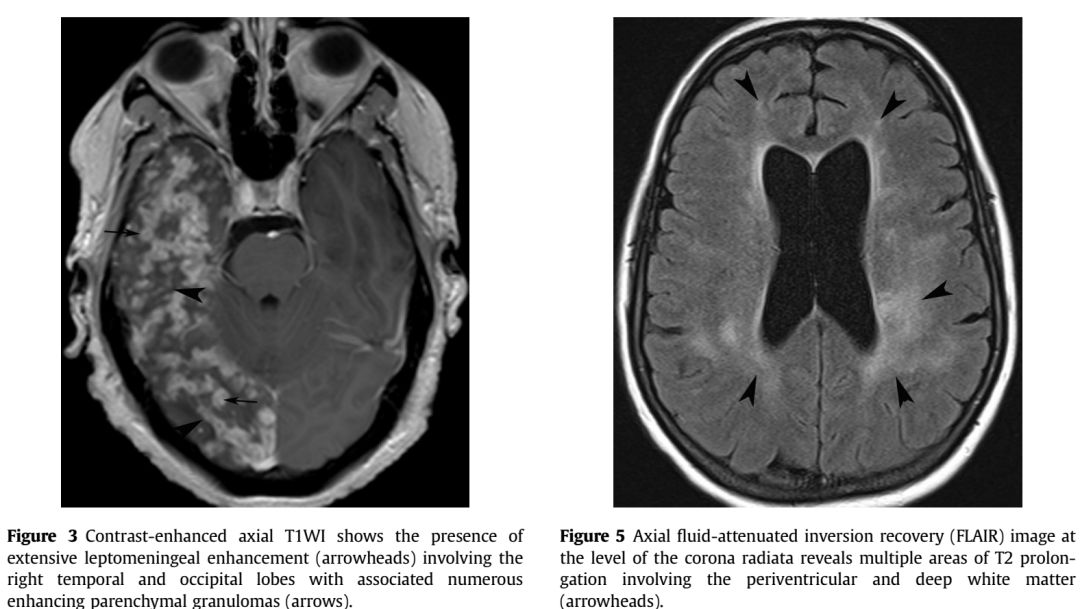

增强序列可见双侧额叶软脑膜明显强化并沿软脑膜侵入沟回,左侧颞顶交界区小片状强化;冠状位及FLAIR可见皮层皮下之白质亦有波及。该病例只有磁共振,且只有FLAIR和增强两个序列,但给人的信息量并不少:脑膜尤其是软脑膜受累突出,伴有皮层、实质损害,强化明显。感染、肿瘤、非感染性炎症都有可能,到底是什么呢?

诊断: 神经结节病

结节病是一种病因不明的多系统肉芽肿性炎症性疾病,年轻人多见。全世界的发病率各不相同,约为10-20/100,000人。它主要影响肺,皮肤和眼睛,神经系统受累约占5-20%。可以说神经结节病是罕见病中的少见表现,但其影像学具有一定的特点,也容易与其他疾病混淆,了解了这些特点在日后不期而遇时不会让它从眼皮下溜走。神经结节病影像学最突出的特点是软脑膜受累,但只知道软脑膜是不足以全面掌握神经结节的影像学表现,关于神经系统其他受累部位及鉴别诊断如下图:

➤脑实质受累(fig3:延血管间隙播散的炎性肉芽肿改变;fig5:脑白质病变):